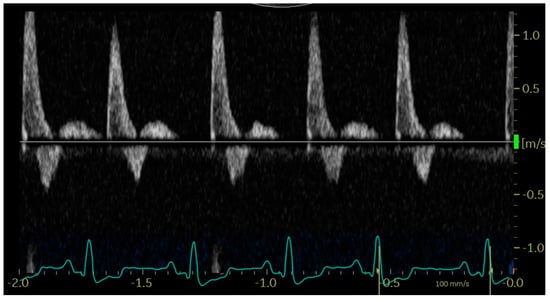

In diastole, when the aortic segment caudal to the renal artery is imaged, a triphasic flow pattern is expected in healthy subjects, characterized by an initial negative deflection followed by a positive rebound and a third phase referred to as end-diastolic flow [21]. Based on the direction of the end-diastolic flow, abdominal aortic flow patterns were classified as one the following three types: antegrade when blood flowed caudally at the end of diastole (Figure 1); absent when no blood flow could be detected at the end of diastole (Figure 2); retrograde when blood flowed cranially at the end of diastole (Figure 3) [11].

Figure 2. Pulsed_wave Doppler ultrasonography of abdominal aortic flow in a dog with left-to-right shunting patent ductus arteriosus showing an absent end-diastolic flow, with the exception of the first cardiac cycle, where the diastole is too short to allow its visualization.